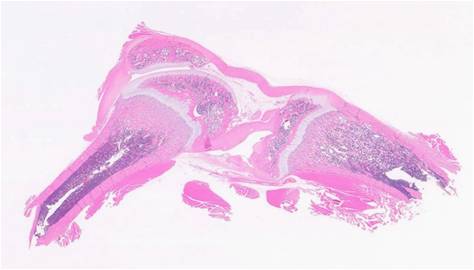

組織構造の観察にご利用ください。(

fig.1

)

fig.1 ヘマトキシリン&エオジン染色(HE染色)